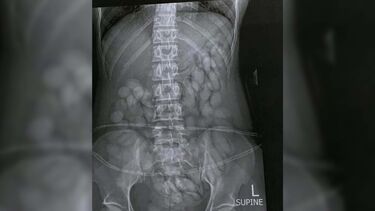

Raio-x mostra estômago de ‘mula de droga’ cheio de cápsulas de cocaína